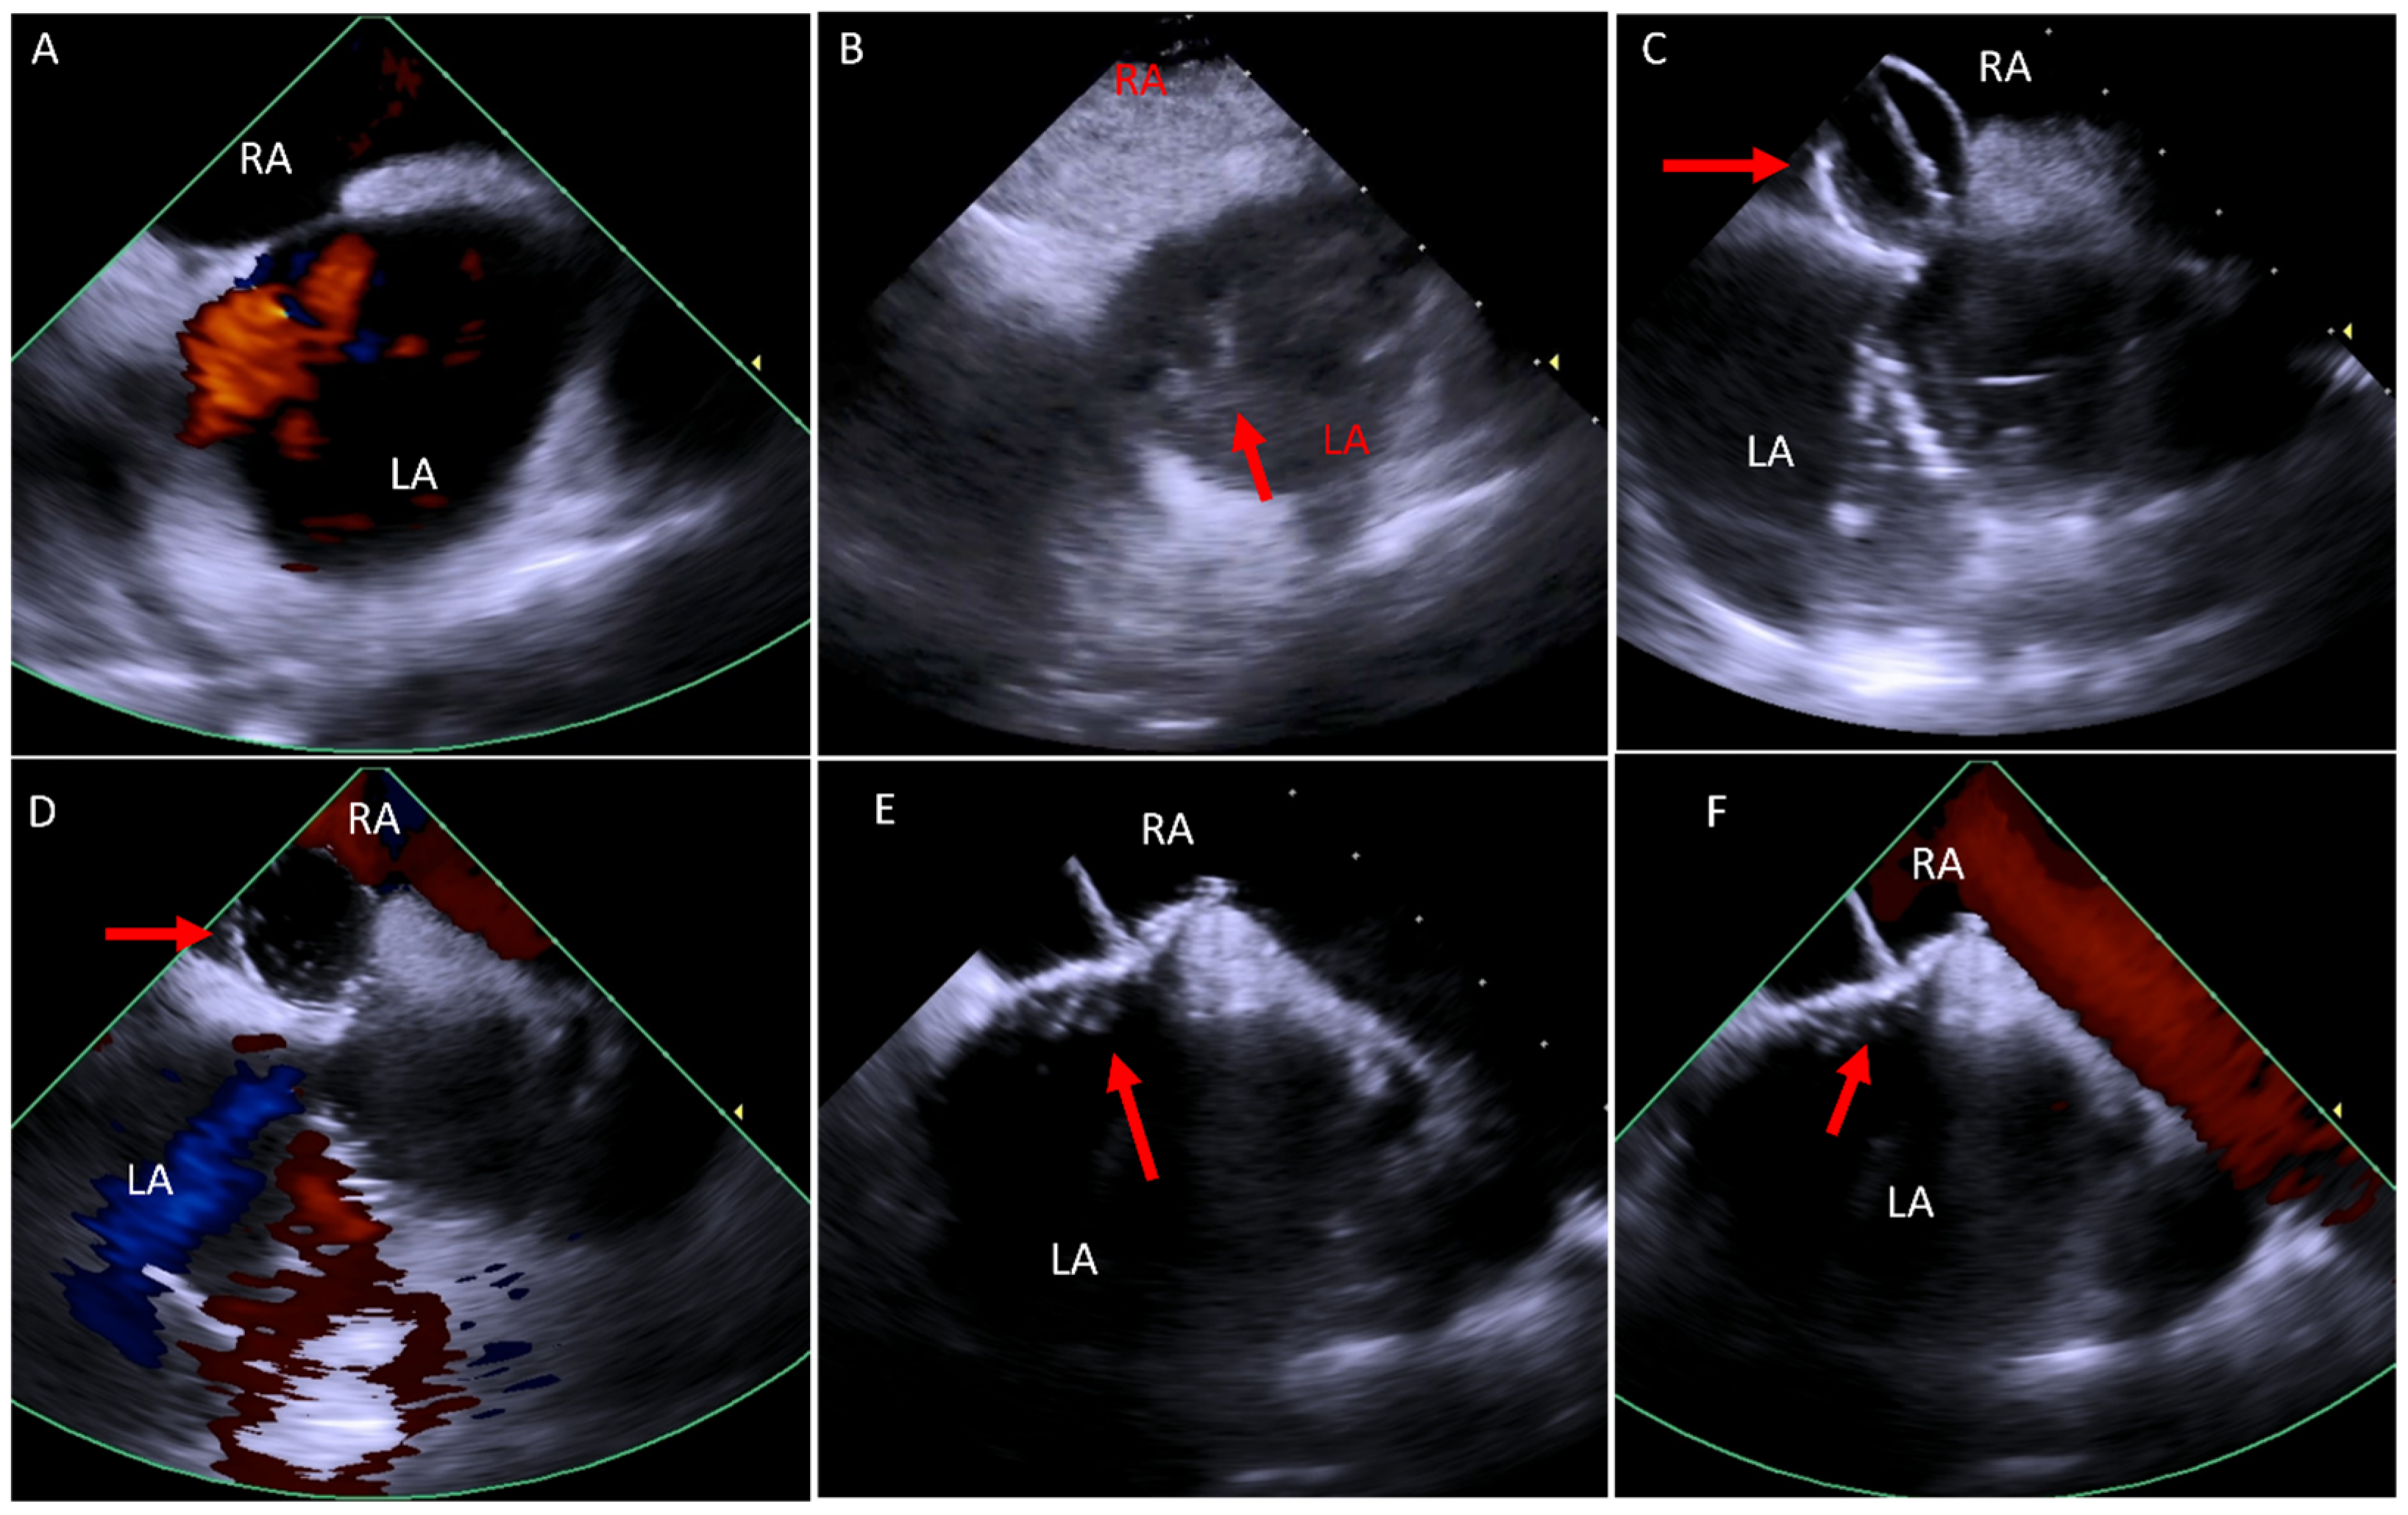

6.1. Baffle Leak Occlusion